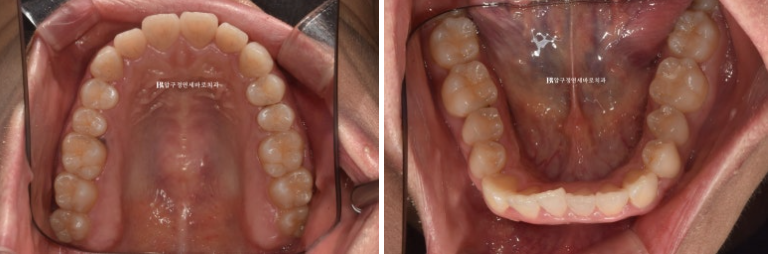

앞니가 삐뚤하고 아래 악궁 모양이 둥글지 않고 네모진 형태입니다.

24.04

추가장치 14개를 4개월에 걸쳐 다 낀 후 모습입니다.

중심선이 맞아지고

송곳니 반대교합이 완벽하게 개선되었습니다.

돌출되어 뻗쳐있던 앞니 각도가 개선이 되면서 돌출감이 개선되었습니다.